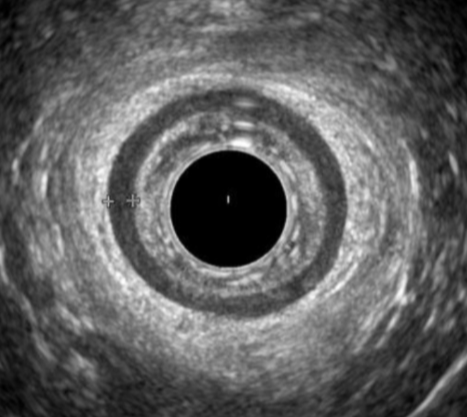

Endoanal Ultrasound

Understand the technique and interpretation of this essential Pelvic Floor modality.